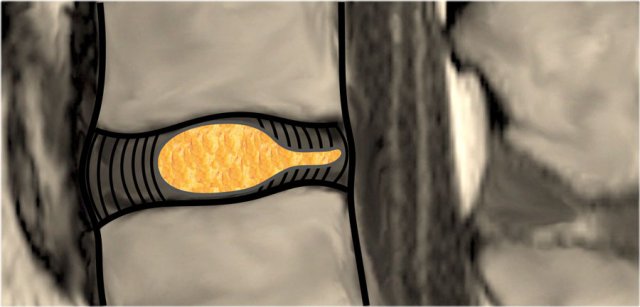

Disc Protrusion versus Extrusion Disc Protrusion versus Extrusion

Protrusion - Extrusion

Protrusion indicates that the distance between the edges of the disc herniation is less than the distance between the edges of the base.

Extrusion is present when the distance between the edges of the disc material is greater than the distance at the base.

Extrusion is associated with a defect in the annulus fibrosus and are usually noncontained.